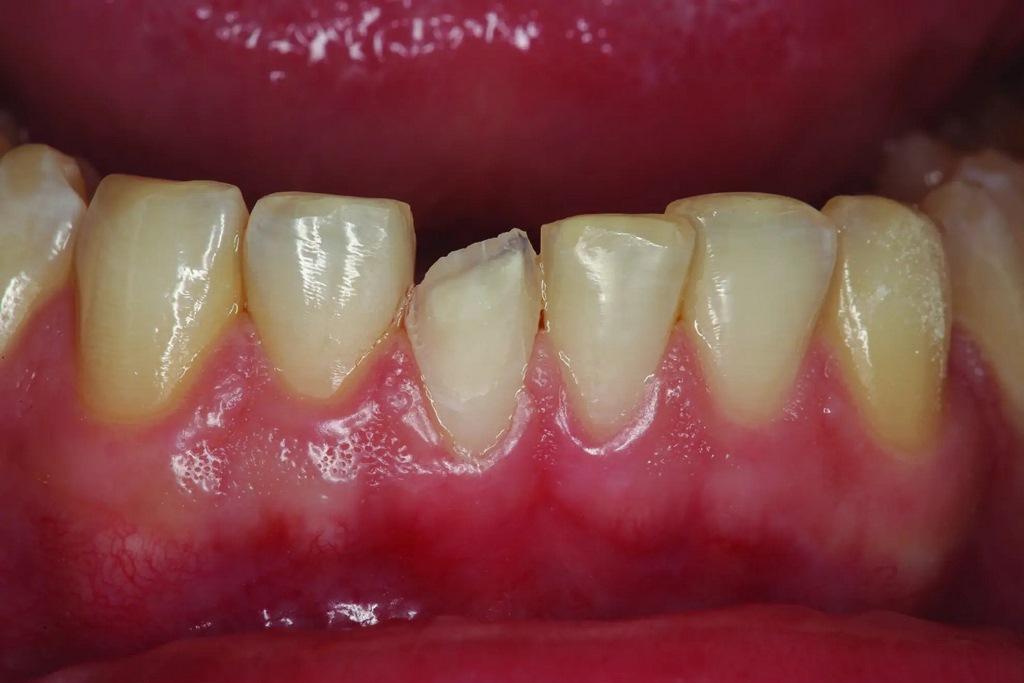

Пациент обратился со сколом композитной реставрации IV класса на зубе 11 по причине дефекта (фото 1). За последний год проводили реставрацию трижды и она снова скалывалась. Было ли это из-за плохой техники или по причине некачественных материалов? Более чем вероятно, что это произошло из-за окклюзии. Помимо большого количества композита на лицевой поверхности, который выходил за пределы области скола, большая часть небной поверхности зуба была стерта до дентина из-за гиперфункции при протрузии и боковом перемещении в течение многих лет, что создавало для пациента функциональную и эстетическую дилемму. «Консервативный» подход, возможно, заключался в том, чтобы снова заклеить зуб композитом и надеяться на лучшее. Однако, возможно, это был не самый лучший долгосрочный подход, учитывая функциональную нагрузку в этой области, даже при наилучшем выравнивании зубов. В конце концов, насколько консервативно постоянное воздействие на зуб вращающимися инструментами для фиксации композита, который продолжает разрушаться?

Фото 1: Предоперационный снимок лицевой стороны реставрации из композитного материала со сколом на зубе 11 в максимально сжатом положении.